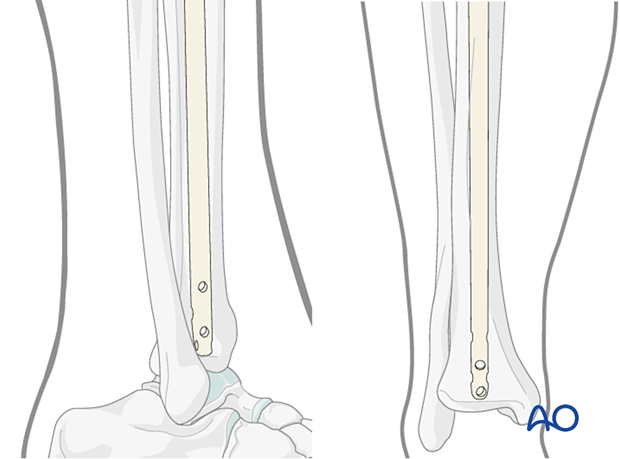

Make sure that the proximal end of the nail is below the surface of the bone at the entry site, to decrease the risk of knee pain. Careful choice of nail length may be necessary, particularly for distal fractures, to ensure both distal fixation and proper length proximally.

The tip of the nail should be placed in the center of the distal tibia, approximately at the level of the physeal scar (denser bone). Distal placement of the nail is particularly important for fractures below the medullary isthmus. Proper fracture alignment must be maintained by the surgeon, since at this level, passage of the nail does not reduce the fracture.

If the length is correct, proximal locking screws are inserted first, and then the insertion handle is removed.

The knee is then extended, and the distal locking is performed, with fluoroscopic guidance using the instrumentation and technique chosen by the surgeon.

Typically, two distal locking screws are used for diaphyseal or proximal fractures, though if the pattern is length-stable, a single screw may be sufficient.

Particularly for distal fractures, multiple screws including AP and/or oblique orientation may be necessary to provide stability. Repeat the above technique as necessary for each screw.